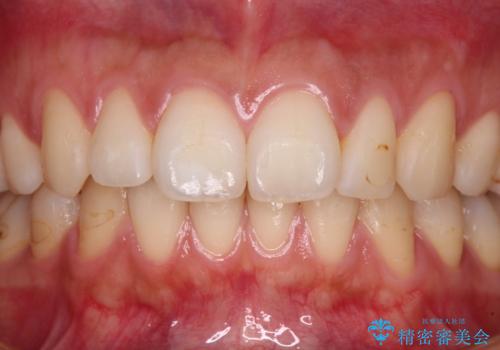

根管治療を行い、その後オールセラミッククラウンにて補綴治療を行うこととしました。

根管治療後速やかに痛みが消退し、6ヶ月後のレントゲン写真では、根尖部の病変がほぼなくなっていることが分かりました。